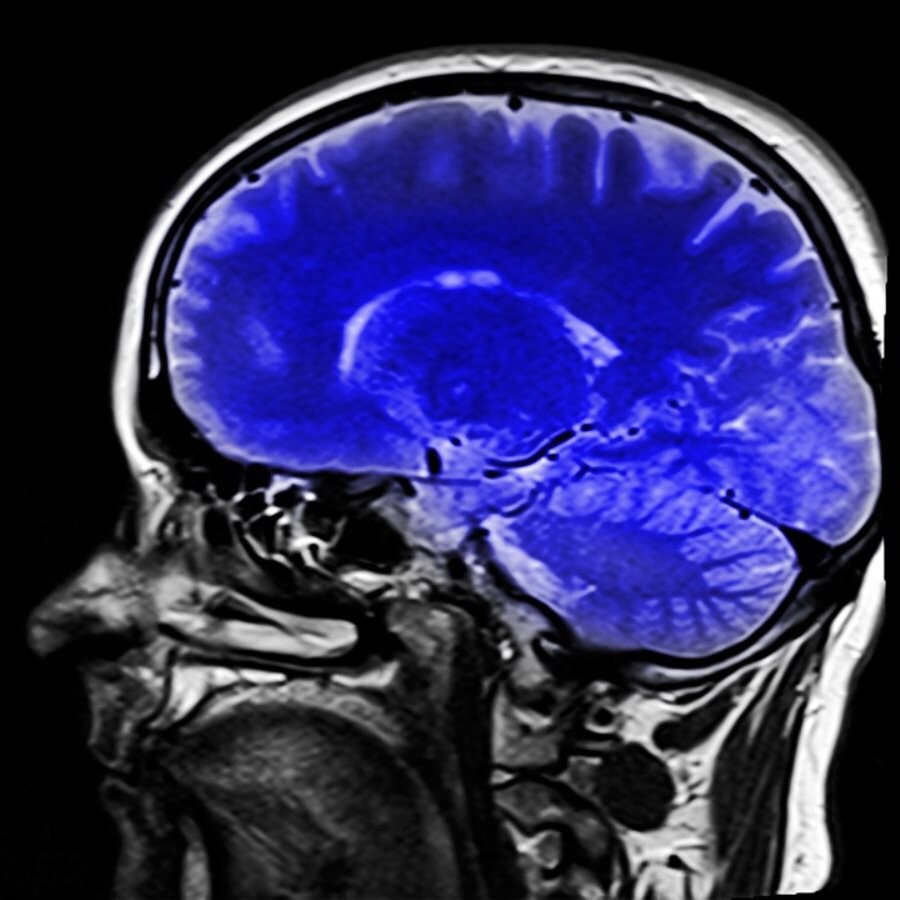

Una nota informativa reciente de la Agencia Española de los Medicamentos y Productos Sanitarios (AEMPS) recomienda dejar de usar gadolinio como medio de contraste en las resonancias magnéticas por haberse observado en pruebas clínicas una acumulación de este producto en el cerebro. Hasta ahora los agentes de contraste con gadolinio se estaban empleando para mejorar la calidad de las imágenes obtenidas mediante resonancia magnética (RM).

Según indica la AEMPS «recientemente, se ha constatado a través de estudios, que algunos de estos agentes de contraste podrían acumularse en el cerebro. Los datos disponibles sugieren que los contrastes con gadolinio de estructura lineal liberan gadolinio en mayor medida que los de estructura macrocíclica. Si bien la significación clínica de la acumulación cerebral de estos depósitos, resulta desconocida, el Comité para la Evaluación de Riesgos en Farmacovigilancia europeo (PRAC), ha recomendado adoptar una serie de medidas».